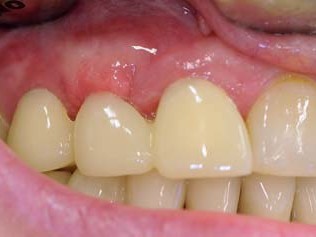

Abb 2 Klinische Ausgangssituation mit Farbwahl

Abb. 2: Klinische Ausgangssituation mit Farbwahl

Die Patientin war seit Jahren mit einer Brückenversorgung gut rehabilitiert. In der Frontzahnregion sollte die frakturierte Zirkonbrücke erneuert werden (Abb. 1 und 2). In der Molarenregion war die Entfernung des Zahnes 25 in Erwägung gezogen worden, um eine erneute Brückenversorgung durchzuführen. Dieses war aber nur mit der Präparation eines weiteren gesunden Zahnes zu erzielen. Eine Implantatversorgung wurde der Patientin nicht offeriert. Die Neuversorgung des Oberkiefers mit einer weiteren Hinzuziehung von gesunden Nachbarzähnen im Sinne einer konventionellen zahnärztlichen Lösung sah die Patientin als nicht mehr zeitgemäß an. So stellte sich die Patientin in unserer Praxis vor.